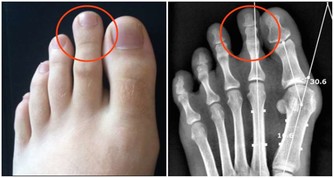

飢餓性酮症

醫學研究證明,如果人體長時間得不到足夠的外源性能量補充,一方面將導致體內脂肪和蛋白質過量分解,造成身體消瘦,長期營養不良,甚至會產生飢餓性酮症;